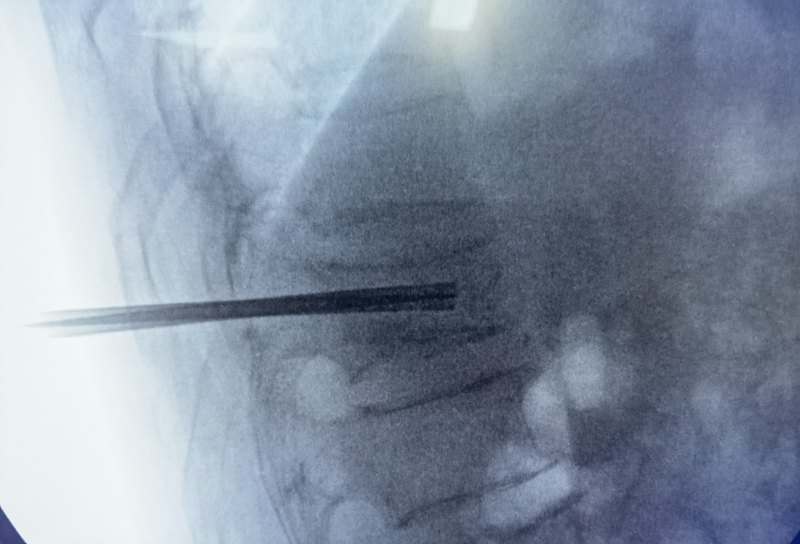

隨著老齡化社會的來臨,高齡和超高齡患者越來越多,骨質(zhì)疏松以及由此引起的骨質(zhì)疏松性脊柱壓縮骨折呈爆發(fā)式增長。脊柱是人體的主要支撐載體,相當(dāng)于房子的承重墻。一旦脊柱發(fā)生骨折,相當(dāng)于承重墻坍塌,人體的重量缺乏支撐,就會出現(xiàn)腰背部無力,疼痛,行走困難,甚至起床翻身這些動作都無法完成,只能長期臥床。PVP手術(shù)即大家熟知的骨水泥填充微創(chuàng)手術(shù),已經(jīng)有40余年的歷史,手術(shù)技術(shù)已經(jīng)十分成熟。PVP手術(shù)是一種局麻手術(shù),患者俯臥在手術(shù)臺,在骨折部位皮膚取一個(gè)3mm的小切口,用直徑2mm的專用細(xì)穿刺針從穿刺點(diǎn)進(jìn)入骨折椎體建立工作通道注射骨水泥。目前最新的手術(shù)方法是,先通過通道在骨折處置入一個(gè)金屬支架把破碎壓縮的椎體支撐起來,這樣就在骨頭內(nèi)形成了一個(gè)低壓空腔,之后再填充骨水泥,骨水泥就會在低壓區(qū)積聚不易滲漏,骨水泥和金屬支架混合,只需要5分鐘即可凝固硬化,永久維持、支撐骨頭的形態(tài),骨折復(fù)位更好、固定更牢靠,就相當(dāng)于用“鋼筋混凝土”把人體的“承重墻”徹底牢固的修復(fù)好了,“承重墻”修復(fù)好后,患者馬上就感覺腰部有力、疼痛緩解、起床翻身就會輕松很多,術(shù)后2小時(shí)就可以下地行走了。—“鋼筋混凝土”強(qiáng)化治療脊柱骨折